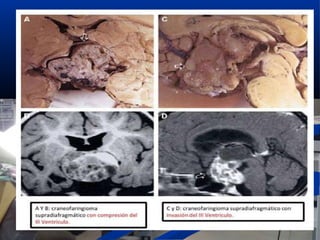

CraneofaringiomaCraneofaringioma

 Edad presentaciónEdad presentación

 2 picos: infancia y adolescencia y edad media2 picos: infancia y adolescencia y edad media

 DerivaDeriva

 restos embrionarios bolsa de Rahtkerestos embrionarios bolsa de Rahtke

 Presentación clínicaPresentación clínica::

 HTICHTIC, alt. visuales, hipopituitarismo,, alt. visuales, hipopituitarismo, DIDI

 Imagen radiológicaImagen radiológica::

 localización supraselar, calcificaciones (50-90%) ylocalización supraselar, calcificaciones (50-90%) y

quistes de colesterol intratumoralesquistes de colesterol intratumorales

 Tratamiento elecciónTratamiento elección: cirugía: cirugía

Craneofaringioma